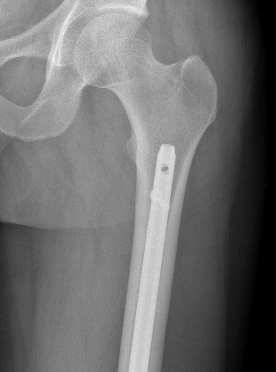

Plate + Nail

Distal Femoral Replacement

Indications

Elderly osteoporotic patient

Unreconstructable distal femur

Multiple co-morbidities

Difficulty non weight bearing

Results

Hart et al. J Arthroplasty 2017

- ORIF v distal femoral replacement in patients > 70 years old

- reoperation rate 10% in both groups

- 20% non union in ORIF

- at one year, 1/4 ORIF patients wheelchair bound, all DFR patients ambulatory